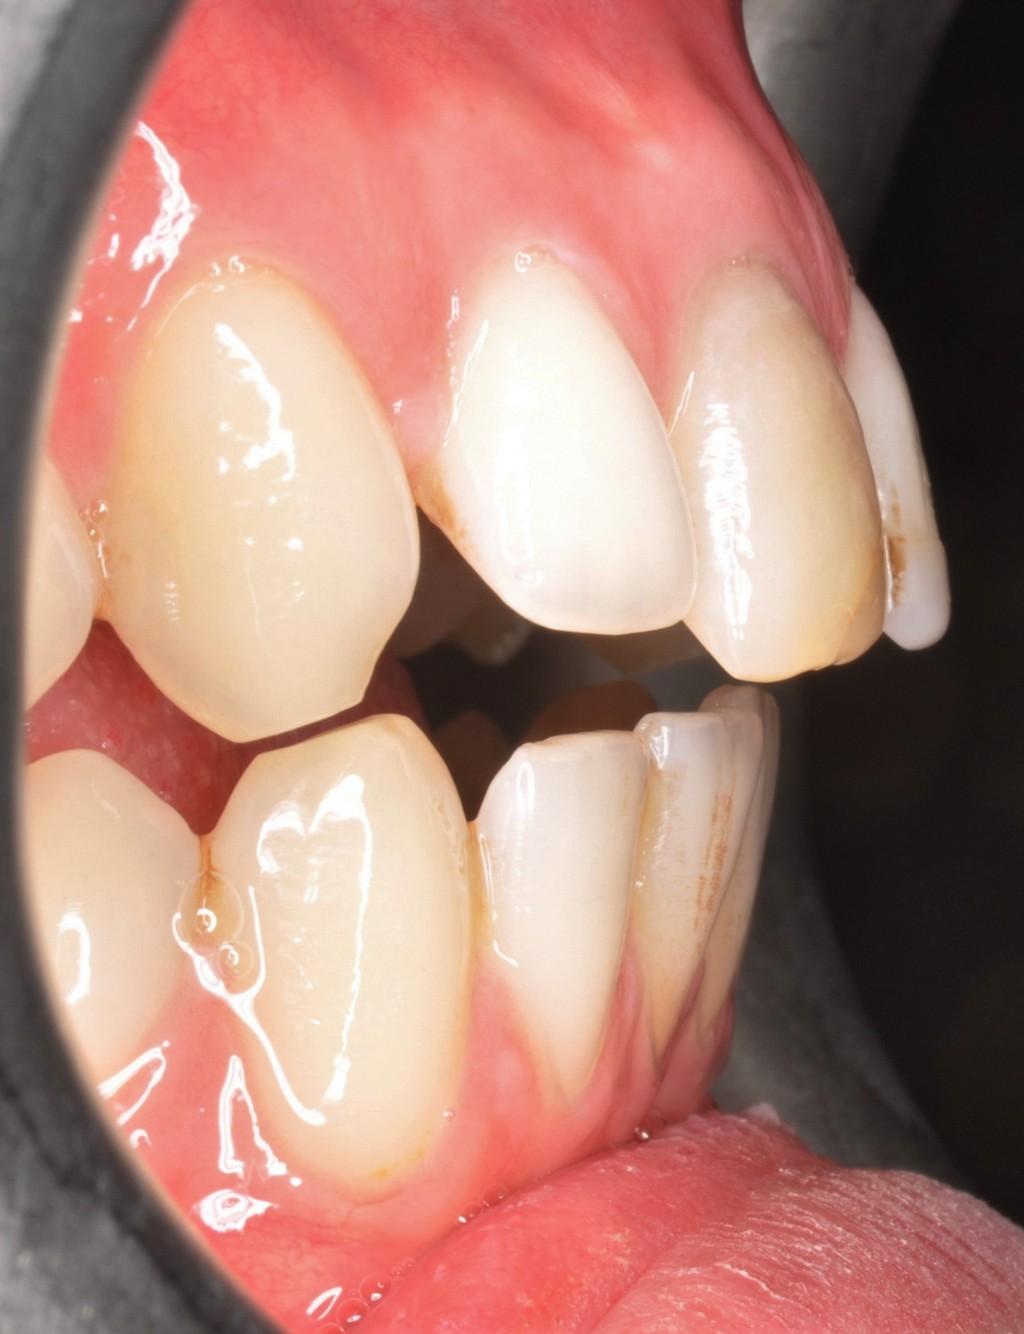

L'apparato stomatognatico, complesso "sistema multifunzione" costituito dalle basi mascellare e mandibolare, dalle arcate dento-alveolari, dal sistema neuro-muscolare e dalle articolazioni temporo-mandibolari, concorre all'espletamento di funzioni vitali per l'individuo, quali deglutizione, respirazione, fonazione e masticazione.

A differenza della Terapia Ortodontica Fissa che si preoccupa soprattutto dell'allineamento dentario, la Terapia Miofunzionale Ortognatodontica Biodinamica si preoccupa di ricreare la funzione, dalla quale ne conseguirà il corretto sviluppo dell'organo. Essa riveste piena dignità scientifica, grazie alle più moderne acquisizioni in tema di crescita e di fisiologia neuromuscolare.

Quest'approccio terapeutico, che "integra contemporaneamente la terapia ortognatodontica e la terapia miofunzionale", mira a correggere le alterazioni funzionali nel bambino e nell'adolescente trattando nel contempo la malocclusione, così come sostenuto dall'Associazione Italiana Miofunzionale Ortognatodontica Biodinamica, tramite l'utilizzo di apparecchiature ortognatodontiche funzionali quali la PFGB, la PFGB2 e la contemporanea messa in atto di esercizi di terapia miofunzionale.